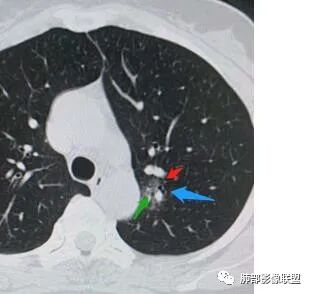

4、血管连通 移动:3型?4型?

两条都进入,相互交通-4

血管进入增粗,胸膜牵拉

金豆

有月牙 两条都进入,相互交通-4 胸膜牵拉

二、看第二个结节

1、密度?

2、边界?

3、收缩力?

4、血管?

5、大小、内部结构、CT值

三、看看这一个

1、密度:PGGN?MGGN?

二.左肺上叶前段磨玻璃结节:

该结节较大,边界清楚,小叶间隔阻挡特征相当明显,微浸润腺癌的诊断几乎没有争议!

三.右肺上叶胸膜下结节及左肺上叶血管旁结节,尽管都是磨玻璃密度,但都比较小且边缘特征不明显,恶性征象未显露,处置并无特殊,定期复查!